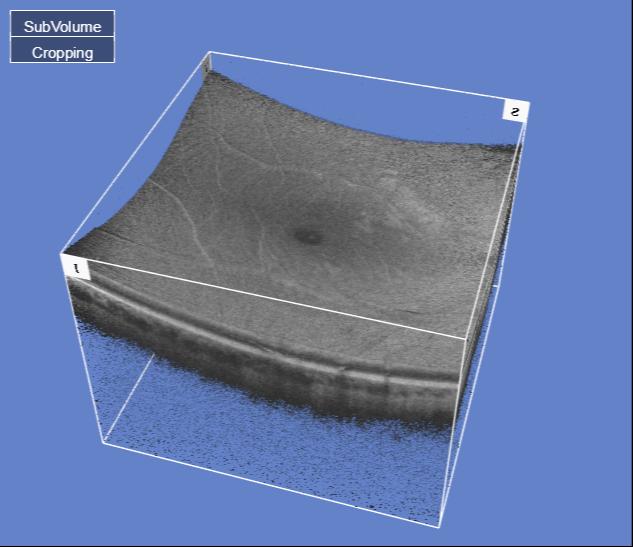

Many high street optometrists and opticians now use retinal scans (OCT machines)

to check the health of the back of your eye (some example images are shown below). Mr Jonathan Park specialises in the review and management of these retinal scans.